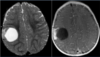

Q

A

Esclerose mesial temporal

Observe a perda de volume, que indica atrofia e causa aumento secundário do corno temporal do ventrículo lateral.

O sinal alto no hipocampo reflete a gliose.

How well did you know this?

Qual o padrão da Esclerose mesial temporal?

Atrofia hipocampal e hipersinal T2. Cerca de 10% dos casos são bilaterais (dificulta o diagnóstico). A etiologia é desconhecida, mas há uma relação entre STM e convulsões febris prolongadas no início da vida A esclerose mesial temporal pode ocorrer em associação com outras patologias, principalmente displasia cortical focal (dual pathology).